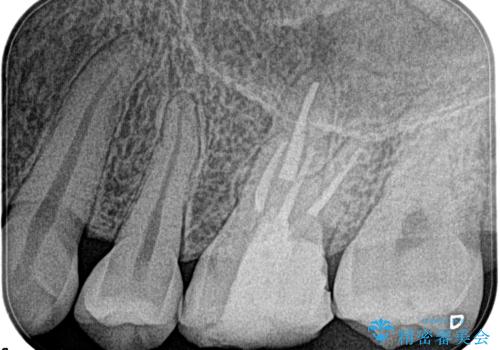

- 奥歯がズキズキ痛いことを主訴に来院されました。

検査の結果、診断を症候性不可逆性歯髄炎、症候性根尖性歯周炎とし抜髄を行っております。

- 精密根管治療(イニシャルケース,大臼歯):122,000円、ファイバーコア:22,000円費用は治療当時の料金となります